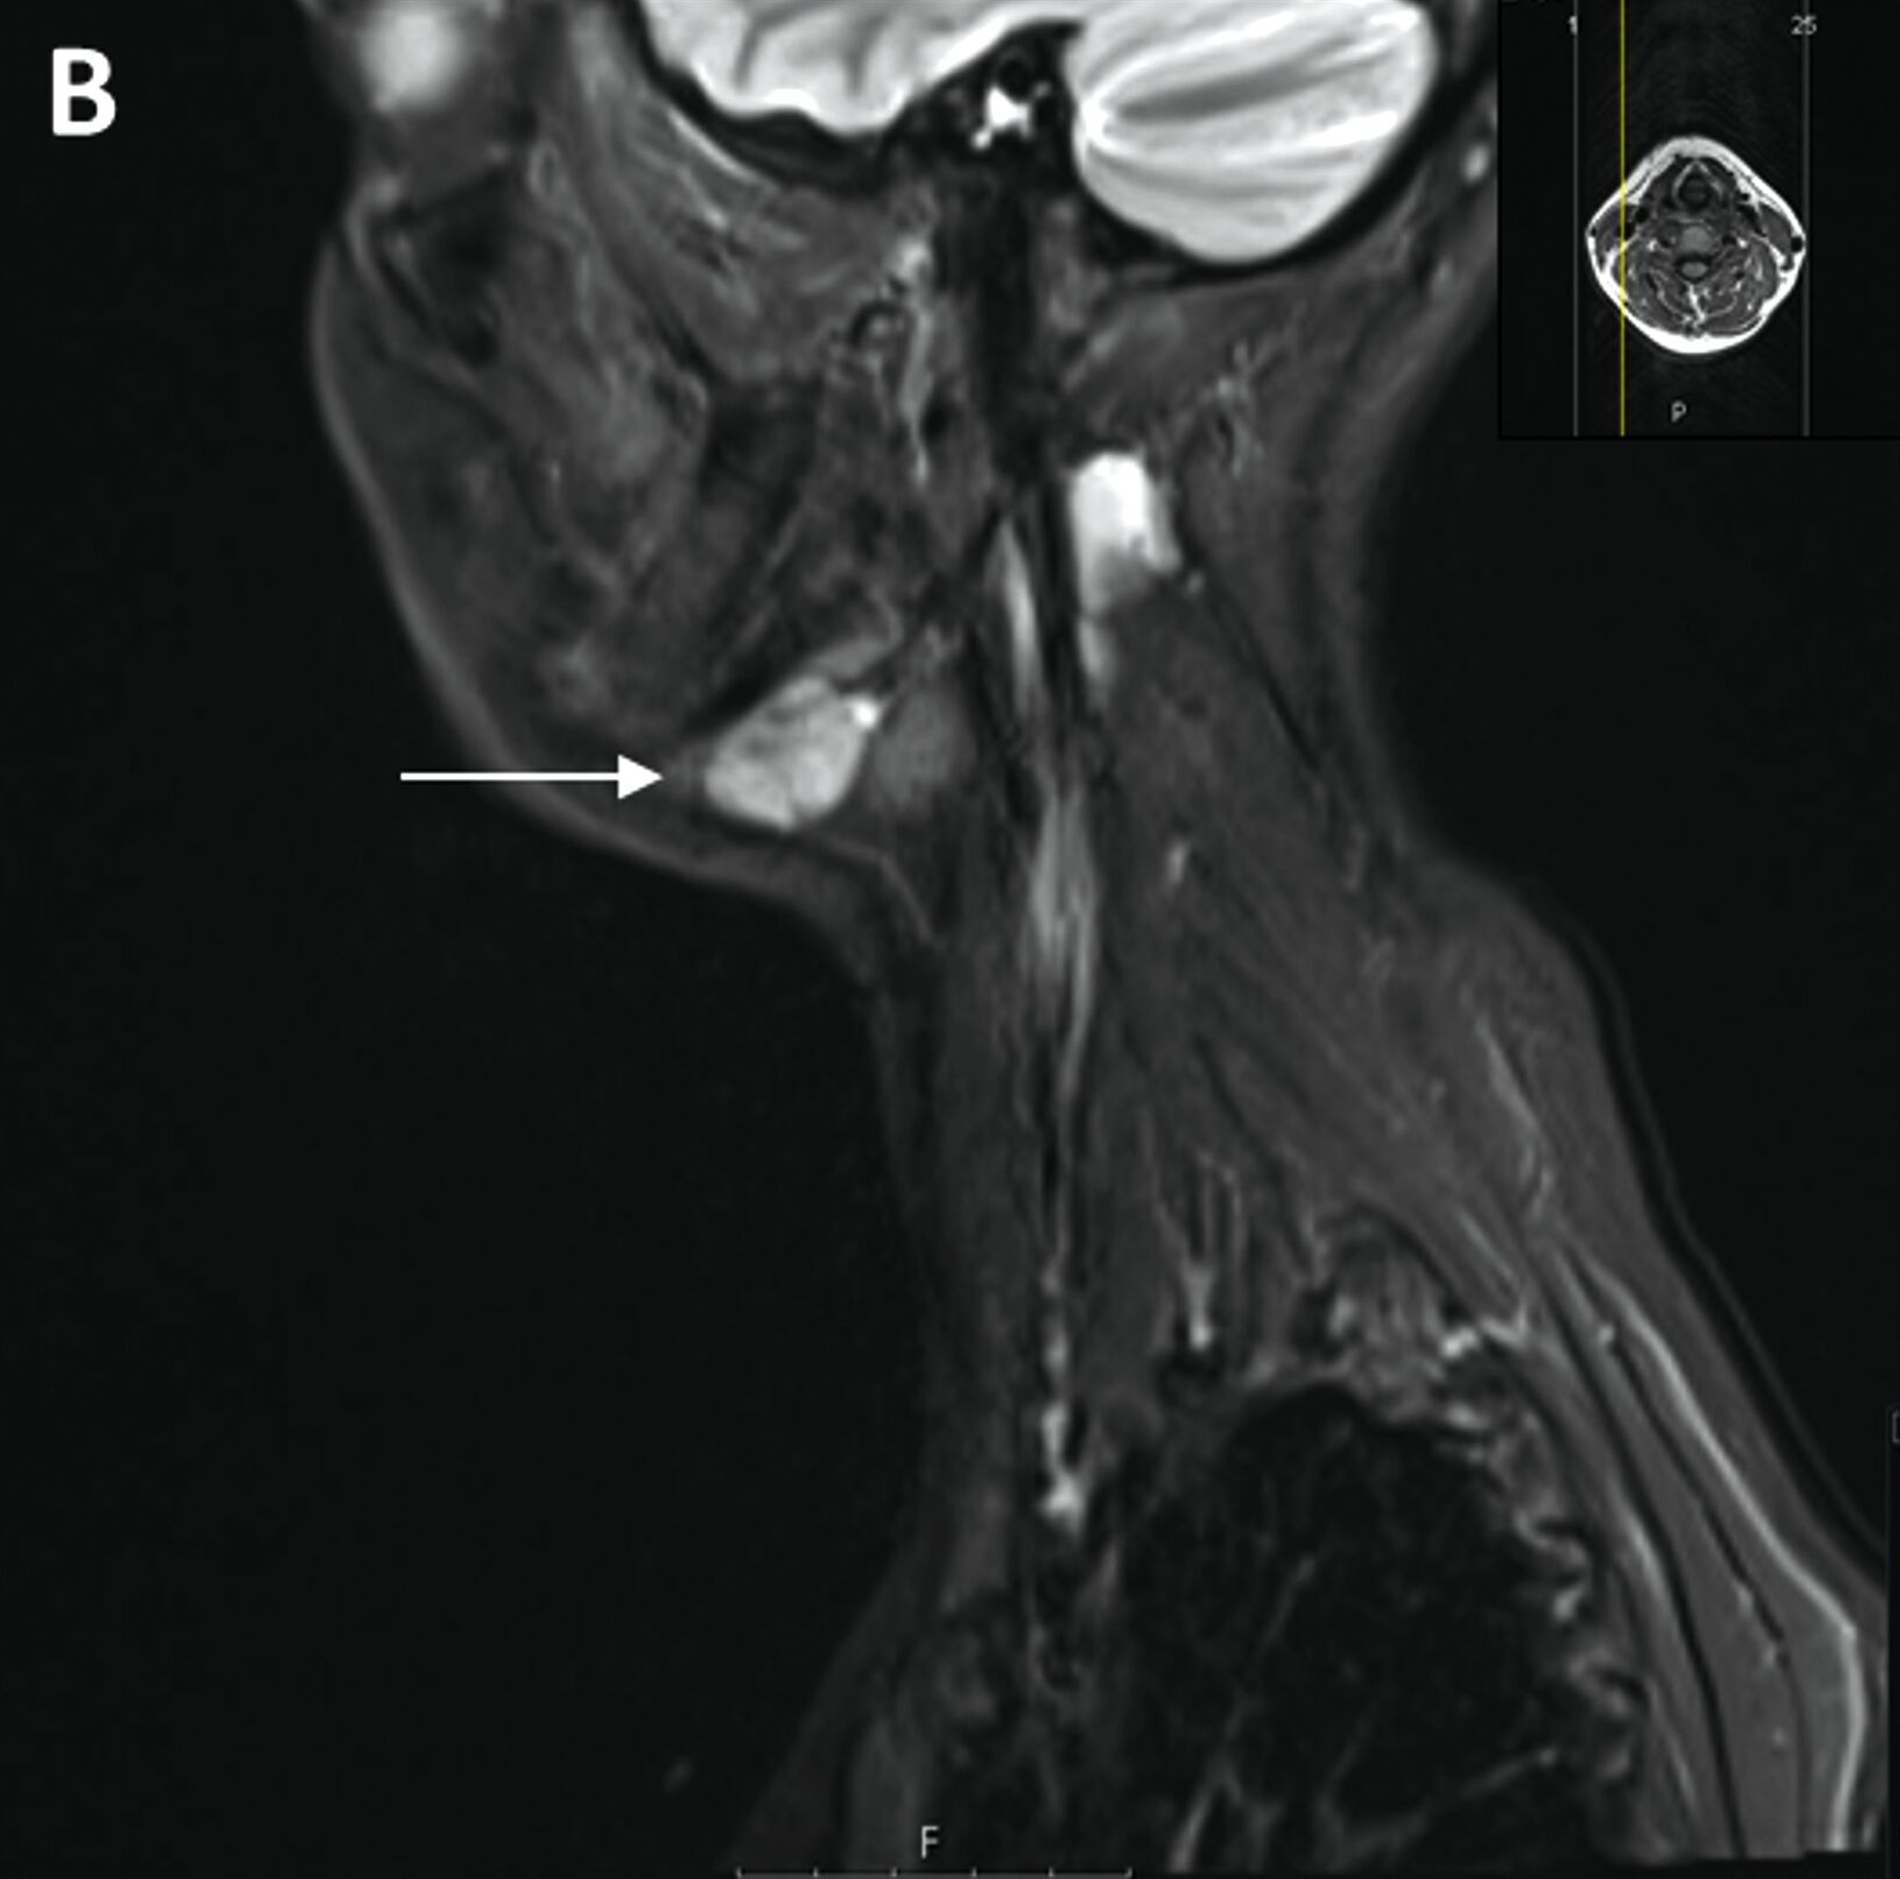

Trotz vorübergehender Remission kam es im August 2023 zu einem erneuten Krankheitsfortschritt mit dem Auftreten eines Metastasen-suspekten Lymphknotens im rechten Halsbereich (Abbildung 1). Bei der chirurgischen Entfernung (Abbildung 2) sowie der histologischen und molekularpathologischen Untersuchung wurde ein kleinzelliges neuroendokrines Lungenkarzinom nachgewiesen (Abbildung 3). Zusätzlich wurden genetische Analysen durchgeführt, die verschiedene Genmutationen und eine Fusion von CTNND1:KMT2A ergaben. Die Therapieentscheidungen basieren derzeit auf den Ergebnissen der molekularen Tumorboarddiskussion.